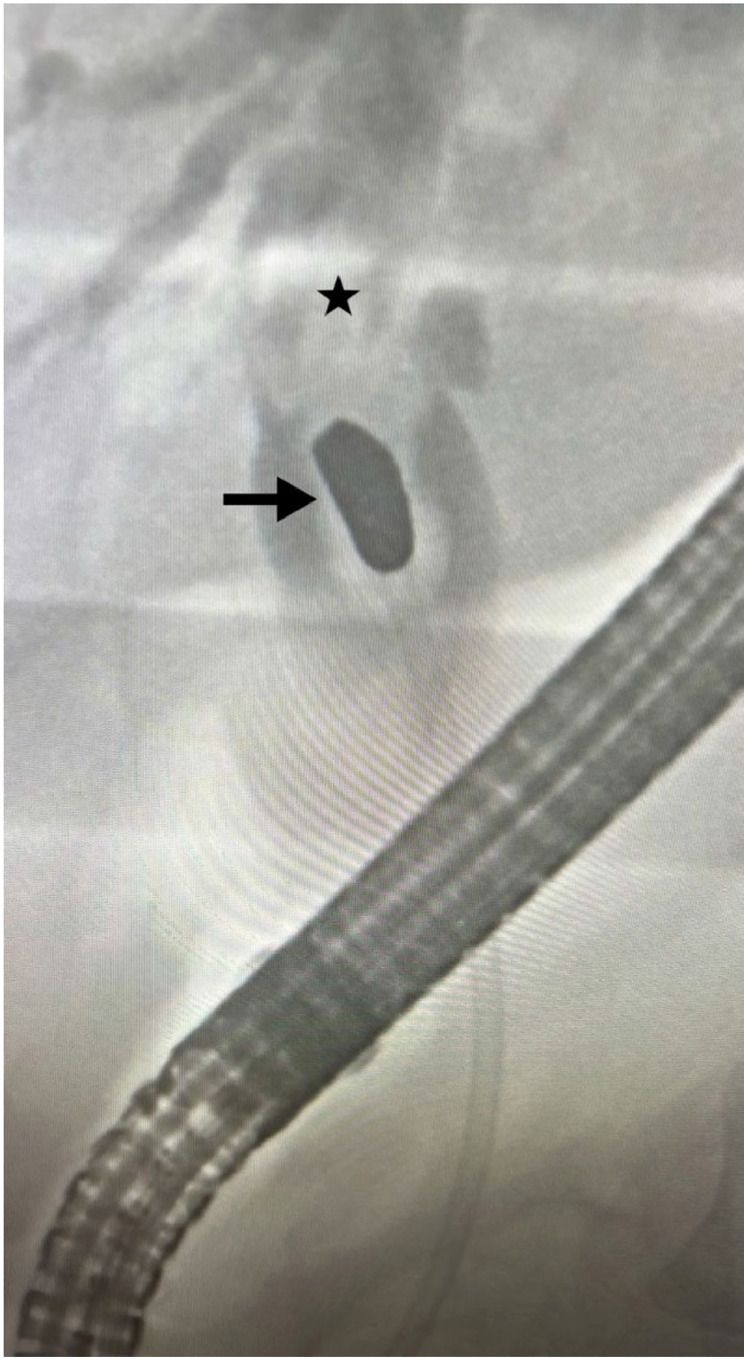

Case presentation: A 41-year-old female with a 13-year history of an accidental gunshot wound, which required an emergency laparotomy, presented to our hospital with symptoms of cholangitis. Endoscopic retrograde cholangiopancreatography was performed, revealing a bullet that caused significant dilation of the proximal bile duct. Exploratory laparoscopy, cholecystectomy, and intraoperative cholangiography confirmed the presence of the bullet. The procedure included a choledochotomy and removal of the bullet, followed by primary closure of the common bile duct using interrupted 4-0 Prolene sutures. The patient was discharged on the 11th postoperative day, and follow-up revealed complete resolution of symptoms and normal liver function.